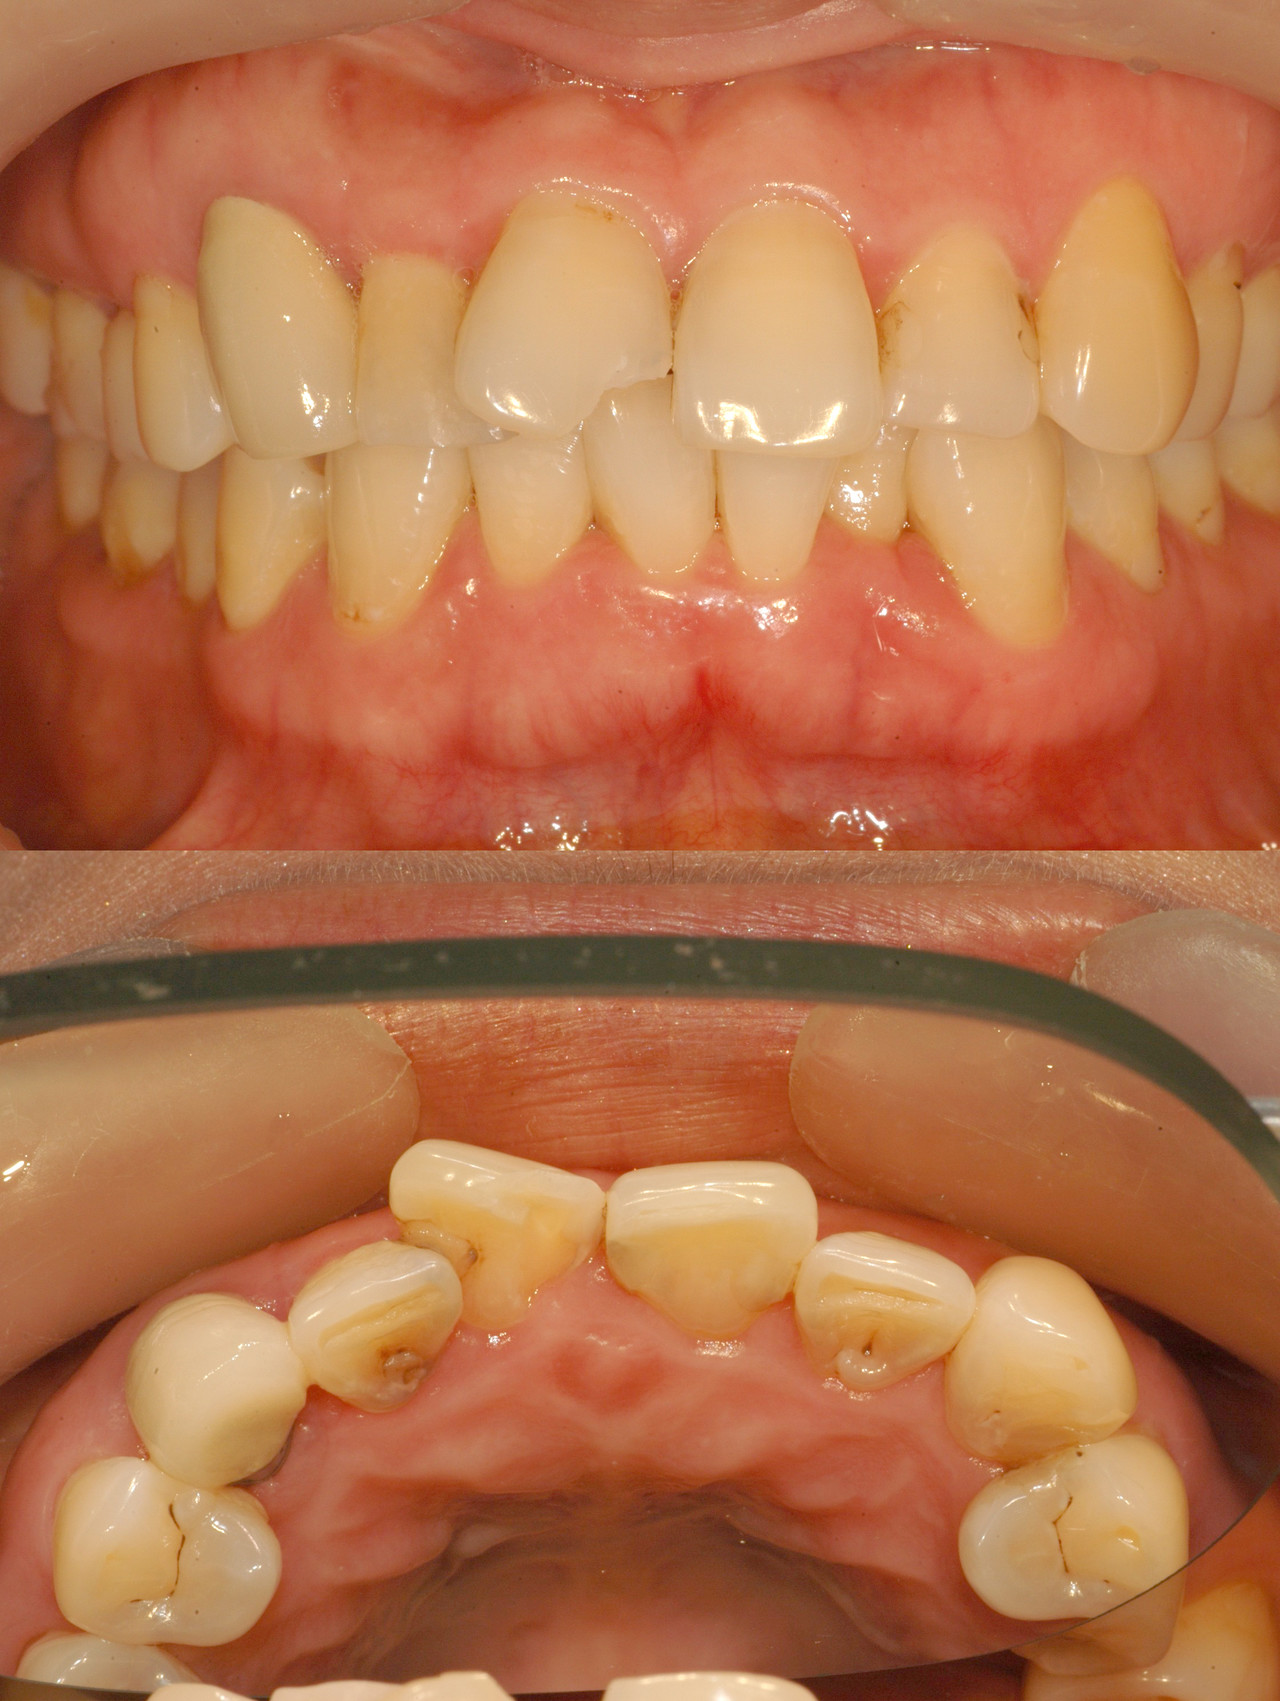

Before & After

> 토브 일반진료 사례

case 01

레진 치료

case 02

인레이 치료

case 03

전악보철

> 토브 협진치료 사례

교정+보철+치은이식

교정+임플란트

Before

라미네이트 시술 전

After

라미네이트 시술 후